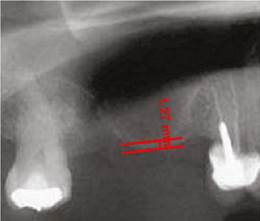

Para realizar el análisis cuantitativo de la zona de interés se digitalizaron todas las imágenes utilizando el programa AxioVision versión 3.1. La altura de hueso e injerto fue medida y ajustada de acuerdo a la magnificación, usando un factor de conversión de 25%. Las medidas iniciales se expresaron en pixeles y posteriormente fueron convertidas a milímetros, usando como referencia una regla milimetrada que fue digitalizada con cada radiografía. Se tomaron las medidas desde el punto de mayor altura de reborde alveolar en la región donde se planeaba colocar los implantes en la siguiente fase, hasta el punto donde se evidencia el cambio en radioopacidad en sentido apical dentro del seno maxilar (Figuras 1, 2 y 3).

Figura 1 Altura residual del reborde alveolar en zona maxilar posterior antes del procedimiento de elevación de piso del seno maxilar

Este estudio comparó la estabilidad de injertos de tibia y de hueso liofilizado (DFDB por sus iniciales en inglés decalcified freeze-dried bone) en procedimientos de elevación de seno maxilar previo a la colocación de implantes. Los resultados obtenidos muestran que los pacientes del grupo en el que se injertó hueso liofilizado presentaron diferencias significativas entre la altura obtenida inicialmente y la altura encontrada 6 meses después de haber realizado el procedimiento. Mientras que en el grupo en el que se utilizó el hueso autólogo de tibia como injerto, la altura inicial no disminuyó de manera significativa durante los 6 meses posteriores a la cirugía de elevación del piso del seno maxilar (Figuras 1 a 3).